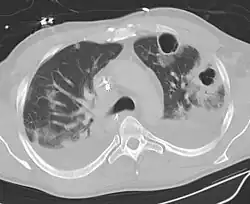

| Computed tomography (CT) scan of chest showing bilateral pneumonia with abscesses, effusions, and caverns. 37-year-old male. | |

Lung abscesses are often on one side and single involving posterior segments of the upper lobes and the apical segments of the lower lobes as these areas are gravity dependent when lying down. Presence of air-fluid levels implies rupture into the bronchial tree or rarely growth of gas forming organism.

Pulmonary abscess on CT scan -